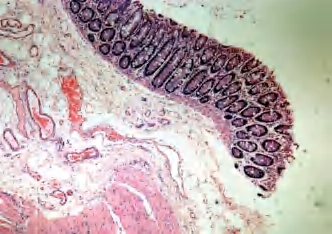

大肠管壁由黏膜、黏膜下层、肌层及浆膜构成(图2-7)。

图2-7 大肠自上而下依次为柱状上皮(固有层)、黏膜肌层、黏膜下层、血管、淋巴管、肌层

1.黏膜层由上皮、固有层和黏膜肌层组成。上皮为富含杯状细胞的柱状上皮。固有层内有散在的孤立淋巴小结。黏膜肌层由内环行和外纵行两层平滑肌组成。

2.黏膜下层为疏松结缔组织,内含较大的血管和淋巴管以及多量脂肪细胞。

3.肌层由内环行及外纵行两层平滑肌构成。内环行肌节段性局部增厚,形成结肠袋;外纵行肌局部增厚形成3条结肠带,带间的纵行肌菲薄甚至缺如。

4.浆膜在间皮下的结缔组织中常有脂肪细胞聚集形成的肠脂垂。